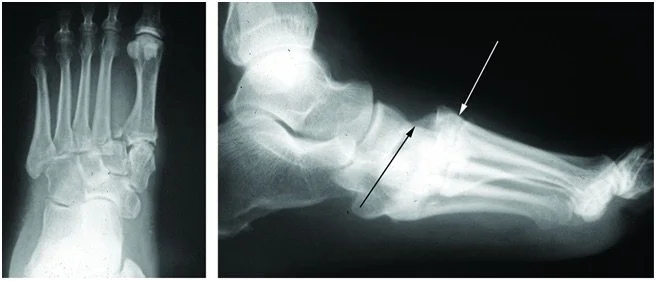

Imaging is critical for accurate diagnosis. Weight-bearing X-rays are often required to identify subtle instability or widening between the metatarsals. CT scans are commonly used to define fracture patterns and joint involvement, while MRI may be helpful for detecting purely ligamentous injuries.